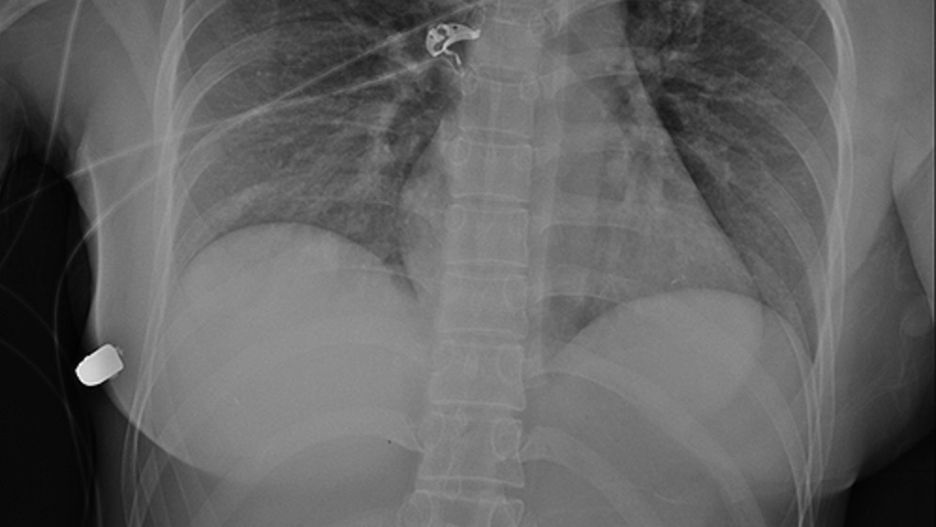

30-letnia kobieta została postrzelona na ulicy w Toronto. Pojechała na lokalny oddział ratunkowy. Lekarze zauważyli, że miała widoczną ranę postrzałową na lewej piersi.

Dalsze badania wykazały jednak, że kula znajdowała się po prawej stronie klatki piersiowej. Lekarze ustalili, że kula przeszła przez lewy implant, a później trafiła w prawy z taką siłą, że obróciła go do góry nogami.

Kobiecie usunięto oba implanty piersi, ale poza złamanym żebrem, nic się jej nie stało. Lekarze doszli do wniosku, że życie kobiety prawdopodobnie zostało uratowane przez silikonowe implanty, które spowolniły pocisk.